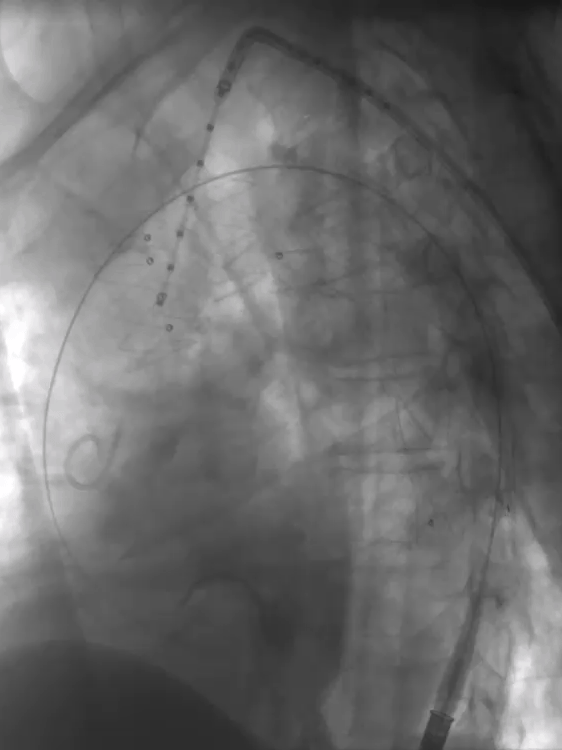

1. 患者仰卧位,常规消毒,铺无菌单,全麻成功后穿刺右侧股动脉,引入短鞘备用;切开左侧肱动脉,穿刺引入导丝,置入8.5F可调弯鞘,引导金标猪尾造影导管至升主动脉水平造影示主动脉弓部巨大瘤样扩张,与术前CT一致。

LAO造影

RAO造影